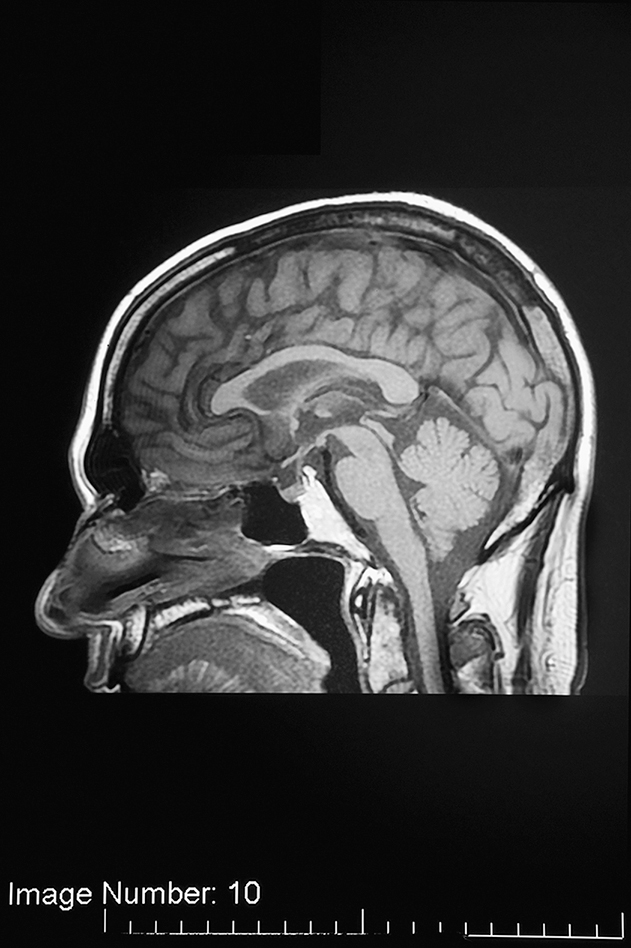

Radio waves are another form of electromagnetic radiation. They are a nonionizing form of radiation and are important in magnetic resonance imaging (MRI) (Fig. 1.3).

MRI uses a strong magnetic field and radio waves along with a computer to generate sectional images of patient anatomy (Fig. 1.11). Like CT, this advanced technology uses highly specialized equipment and requires specialized education. Although many MRI technologists have obtained their education through continuing education courses and on-the-job clinical experience, formal educational programs now exist with baccalaureate, associate, or certificate credentials. For the most part, MRI technologists have credentials in radiography and many are also experienced CT technologists. In 1995 the ARRT began offering a post-primary pathway for the certification examination in MRI. To qualify to take the examination, individuals must be ARRT certified in radiography, nuclear medicine technology (or NMTCB certified), radiation therapy, or sonography (or ARDMS certified) and meet clinical requirements. Candidates can also become eligible to take the primary magnetic resonance examination by completing a formal educational program in MRI approved by the ARRT. There are approximately 65 ARRT-recognized educational programs in MRI. Effective January 1, 2015, all candidates must have earned an academic degree to qualify for this certification. An ARRT-certified individual uses the initials R.T.(MR) after their name.